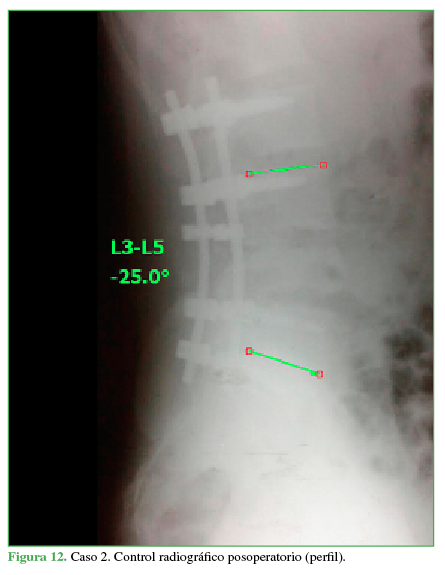

Se decide el tratamiento quirúrgico con abordaje posterior lumbosacro, reducción, descompresión posterolateral directa por técnica tipo eggshell y artrodesis lumbosacra larga L2-S1 (Figuras 11 y 12).

Control radiográfico posoperatorio (perfil)

PropiaEl paciente evoluciona favorablemente, con recuperación neurológica completa. Se corrige la cifosis segmentaria con medición radiográfica a los seis meses de la cirugía adecuada (Cobb L3-L5 25°, lordosis lumbar 39°, incidencia pelviana 40°, IP-LL 1°, inclinación de la pelvis 8°).